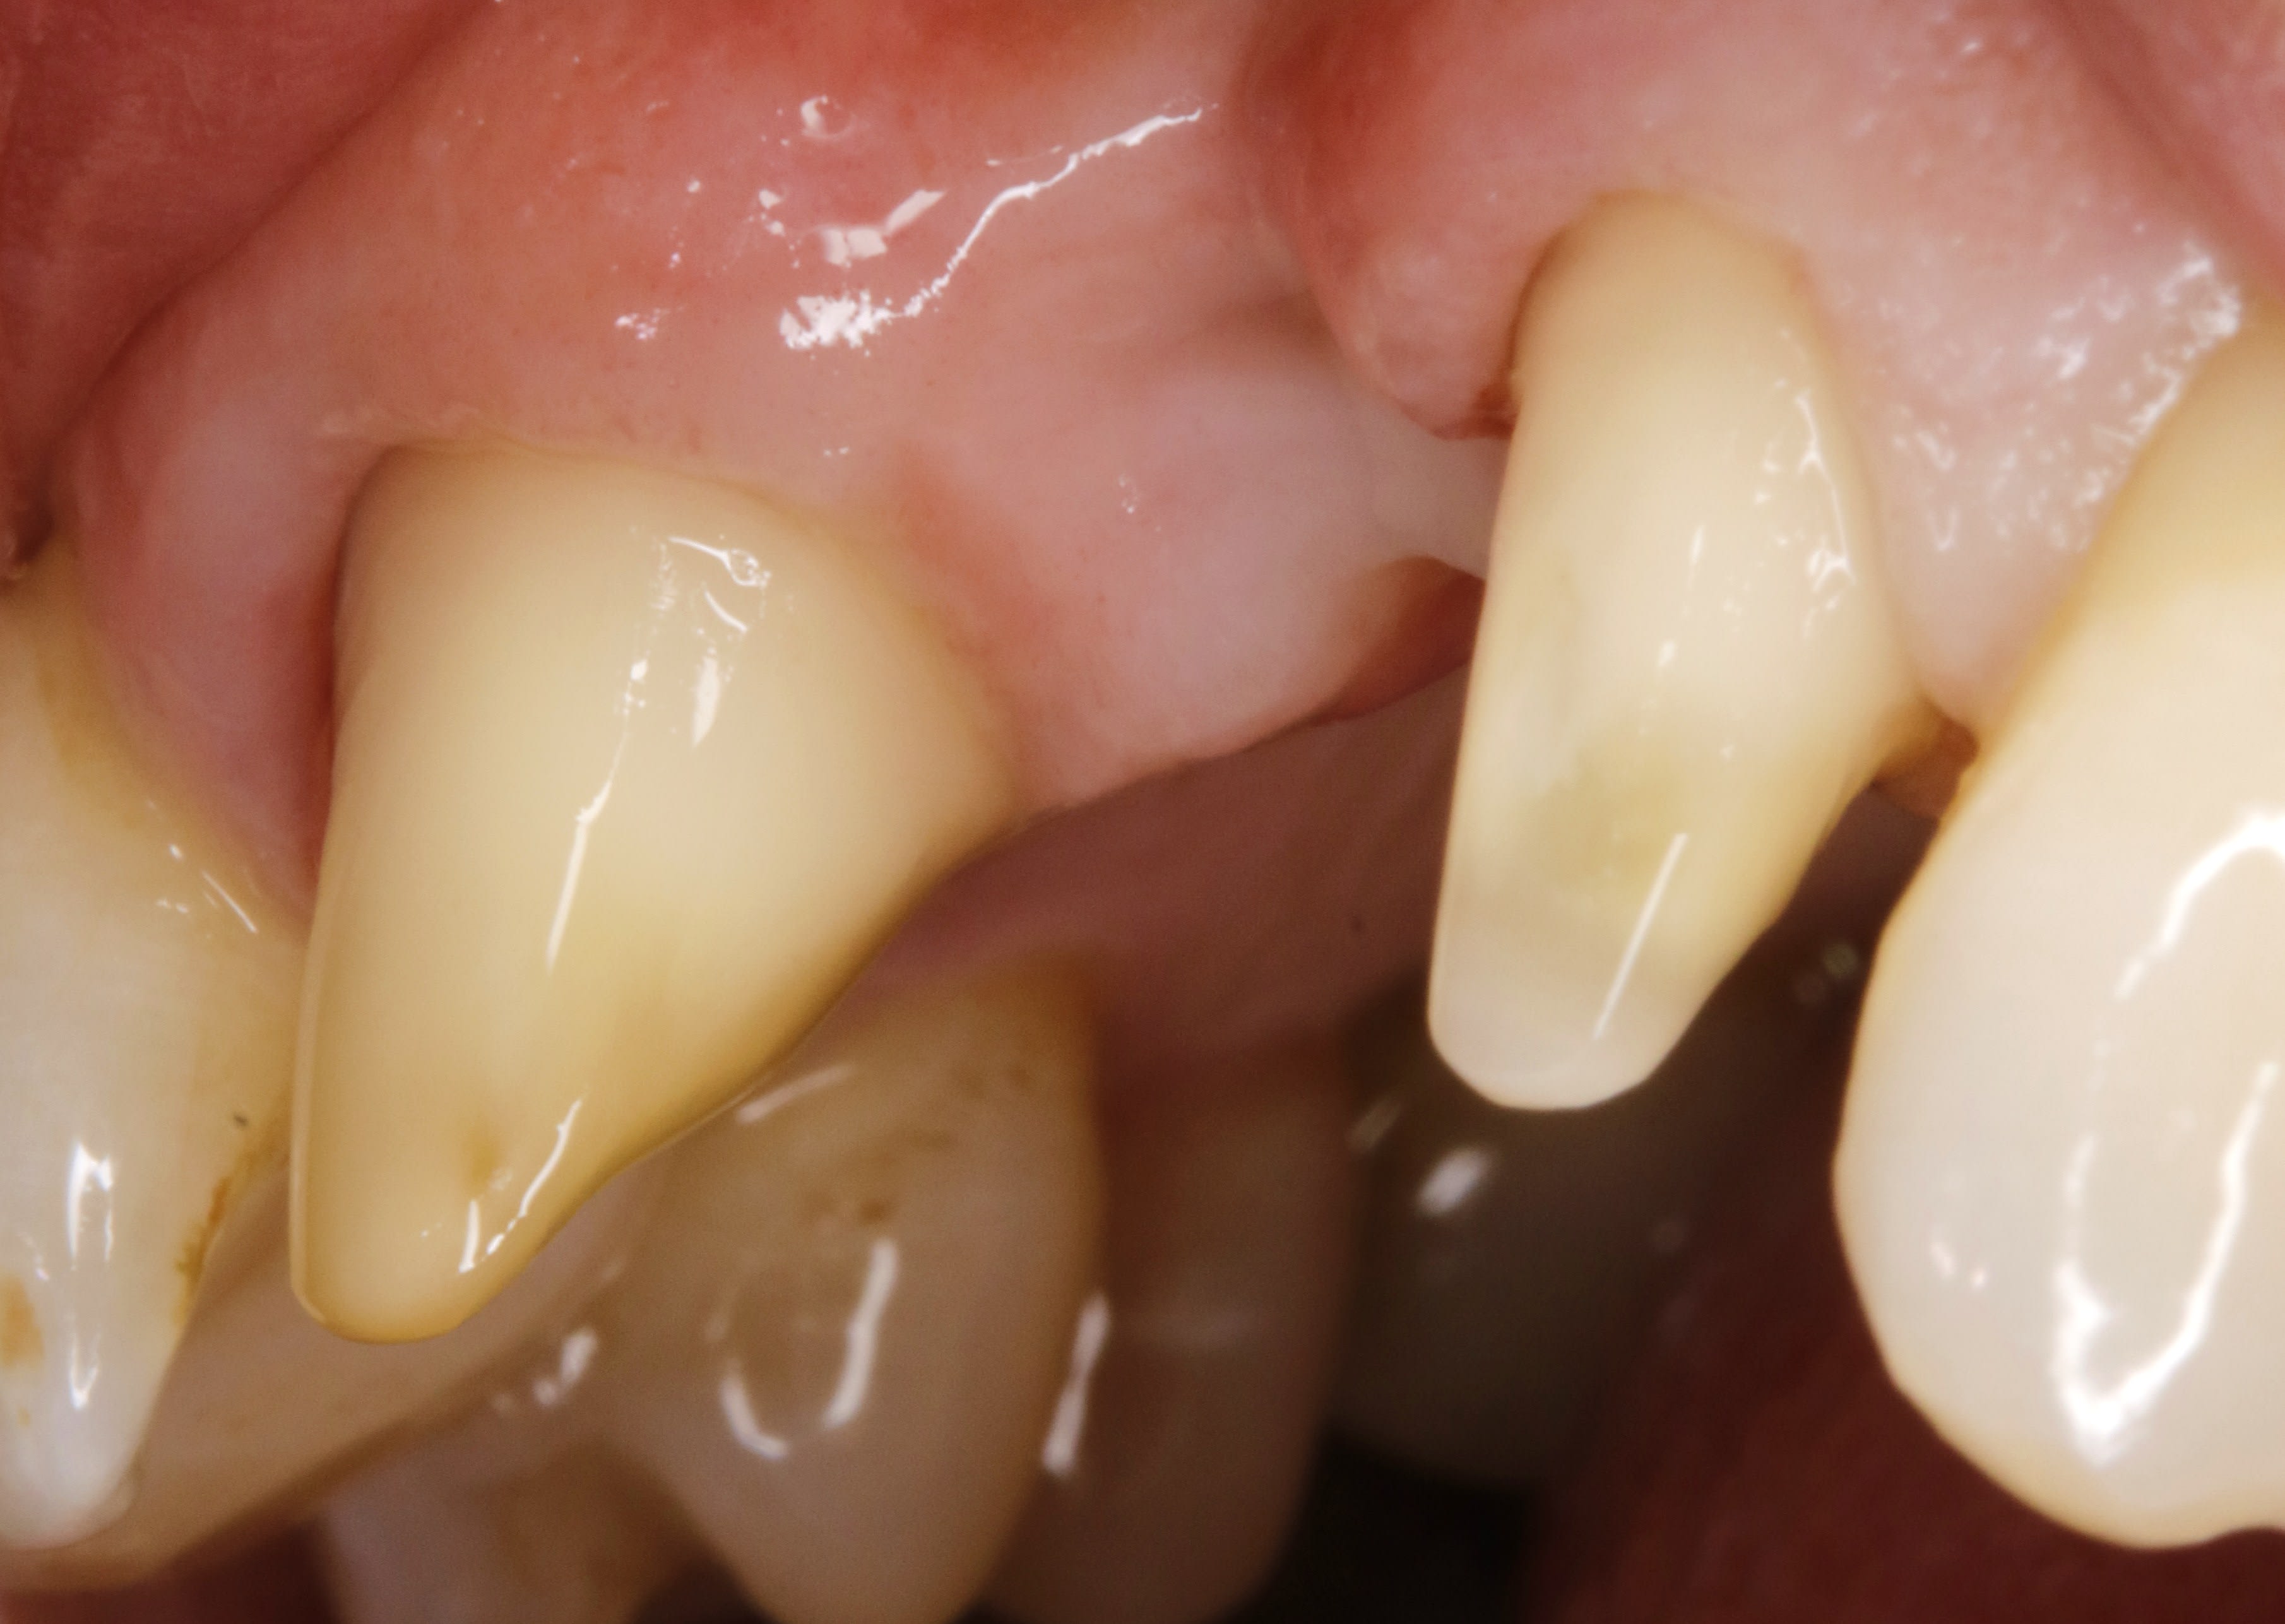

par exemple ce cas :

là le depart des racines est concave , et en plus la gencive est à ras .

Fil1 o23suu - Eugenol